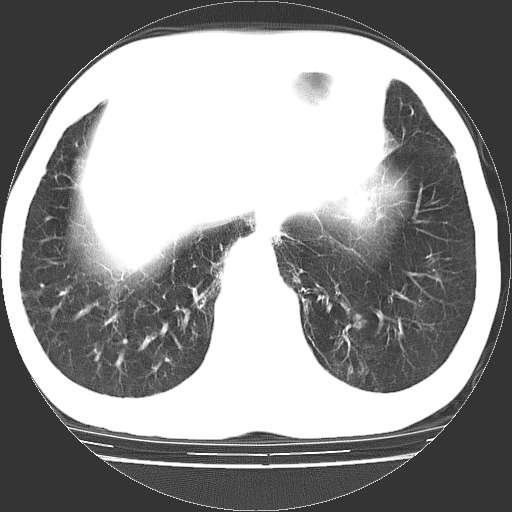

以下是引用hhcckk在2009-1-1 15:38:00的发言:[br]左下肺少许絮状模糊影--考虑感染[br]两肺散在小点状密度增高影--结合病史考虑矽肺?[br]气管壁钙化--可能由于老年退变性引起的